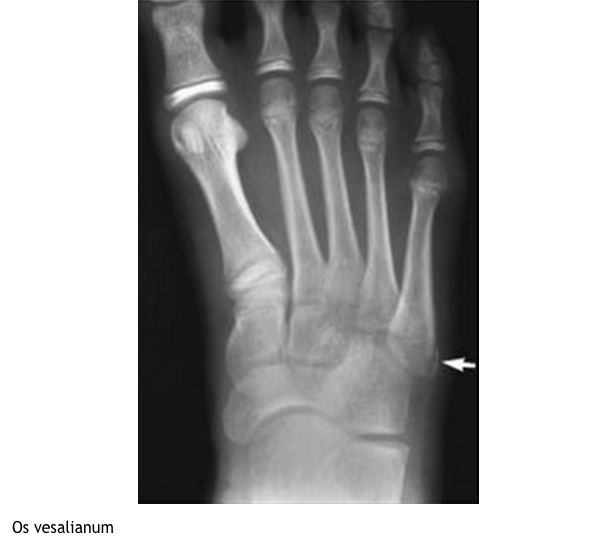

What is this?